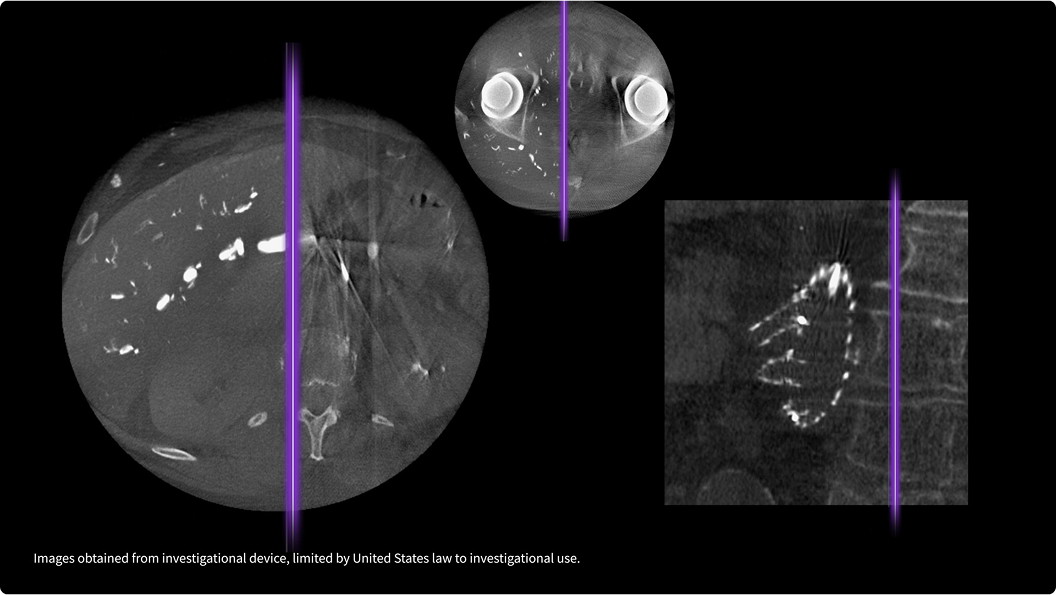

Abbiamo costruito Omni Legend in ogni sua parte per sfruttare la potenza di dBGO, un innovativo materiale del rilevatore con un cristallo di piccole dimensioni in grado di produrre immagini ad alta risoluzione con una qualità eccezionale. In questo modo si crea una nuova categoria di tecnologia dei rilevatori che offre una sensibilità più che doppia rispetto ai precedenti scanner digitali,4 consentendo scansioni rapide5 a una dose inferiore.6 Il risultato finale è un design straordinario, oggi più accessibile a un numero maggiore di persone, e un rilevatore progettato per aggiornamenti futuri che consentano una scalabilità del campo di vista assiale fino a 128 cm.

*Omni Legend e Precision DL recano il marchio CE. Omni Legend ha ricevuto l'autorizzazione 510(k) da parte della FDA statunitense. Precision DL è in attesa di autorizzazione 510(k) da parte della FDA statunitense. Non disponibile per la vendita negli Stati Uniti. Qualsiasi immagine clinica mostrata elaborata con Precision DL è stata ottenuta da un dispositivo sperimentale, limitato dalla legge statunitense all'uso sperimentale.